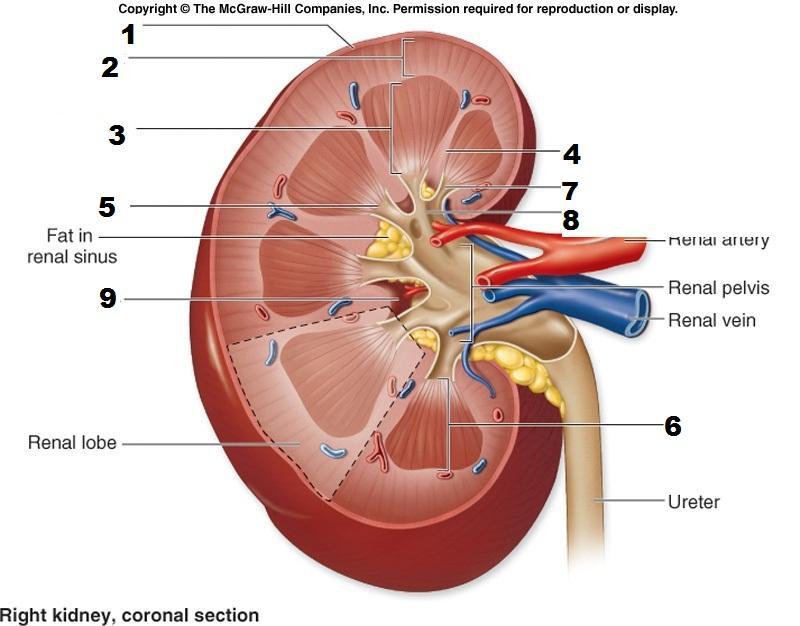

Calyx (of the kidney)

Kidney

Medullary pyramids

Renal artery/vein

Renal capsule

Renal columns

Renal cortex

Renal medulla

Renal Pelvis

Ureter